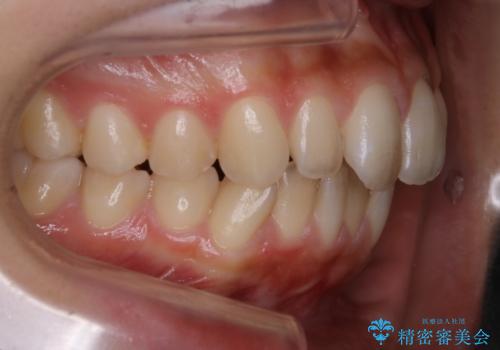

- 前歯の歯並びの改善を希望され来院された患者様です。

初診時の歯並びの状態としては、上下ともに全体に及ぶの中等度のがたつき(叢生)があり、全特に左上の前歯は1本だけ引っ込んでいる状態でした。

抜歯は行わず上顎の奥のスペースを利用して歯をスライドする方法の他に歯列弓の拡大やディスキング(歯と歯の間の隙間を作る処置)を行い叢生を改善しました。

歯の大きさの不揃いが原因の正中のズレは、ディスキング量を調整することで合わせています。

上の歯を後ろに送る方法として、歯茎に入れた小さなネジからゴムかけをして歯列全体を後ろに引っ張りました。